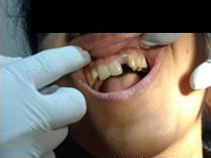

Pre Operation

Single Tooth Implant